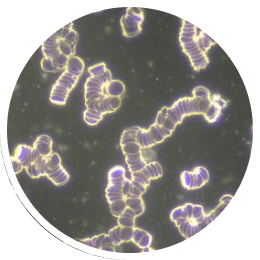

Tässä verinäytteessä on nähtävissä solukonglomeraatteja kolikkorullien muodossa. Tämä on tyypillinen merkki matalasta solukalvojännitteestä.

Tässä kuvassa on verinäyte samalta potilaalta vain 15 minuutin papimi -hoidon jälkeen.

Ioni-induktiokenttä stimuloi kehon heikentyneet solut ja nostaa ne terveeseen jännitepotentiaaliinsa. Solu voi jatkaa säätelyprosesseja ja vaihtaa hivenaineita.

©Prof. Dr. med. Thomas Rau